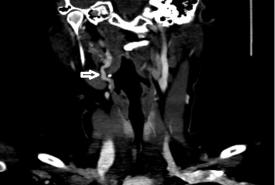

Unilateral Pulsatile Tinnitus in Young Female Adults: A Report of Two Cases

Case Report 21 Jul, 2025